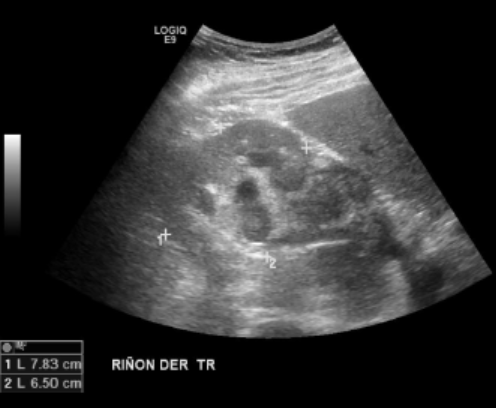

Se observa el riñón derecho aumentado levemente de tamaño con una hidronefrosis moderada. Adyacente al riñón se observa una masa isoecogénica respecto a la cortical renal, heterogénea, de bordes mal definidos, con señal periférica al Doppler, de presunto origen ureteral.

Moderada hidronefrosis derecha, secundario a lesión sólida pieloureteral, hipoecogénica y heterogénea. Mide 6,2 x 4,8 x 8,1 cm, vascularizada.

Moderada hidronefrosis derecha, secundaria a la lesión pieloureteral, de aspecto primario.

Indispensable complementar con estudio con Urotac